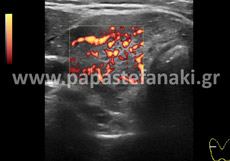

Με την έγχρωμη υπερηχοτομογραφία (Triplex) μπορούμε να ελέγχουμε την ροή του αίματος μέσα στα αγγεία του σώματος όπως η αορτή, οι καρωτίδες, οι νεφρικές αρτηρίες, οι φλέβες και αρτηρίες άνω και κάτω άκρων